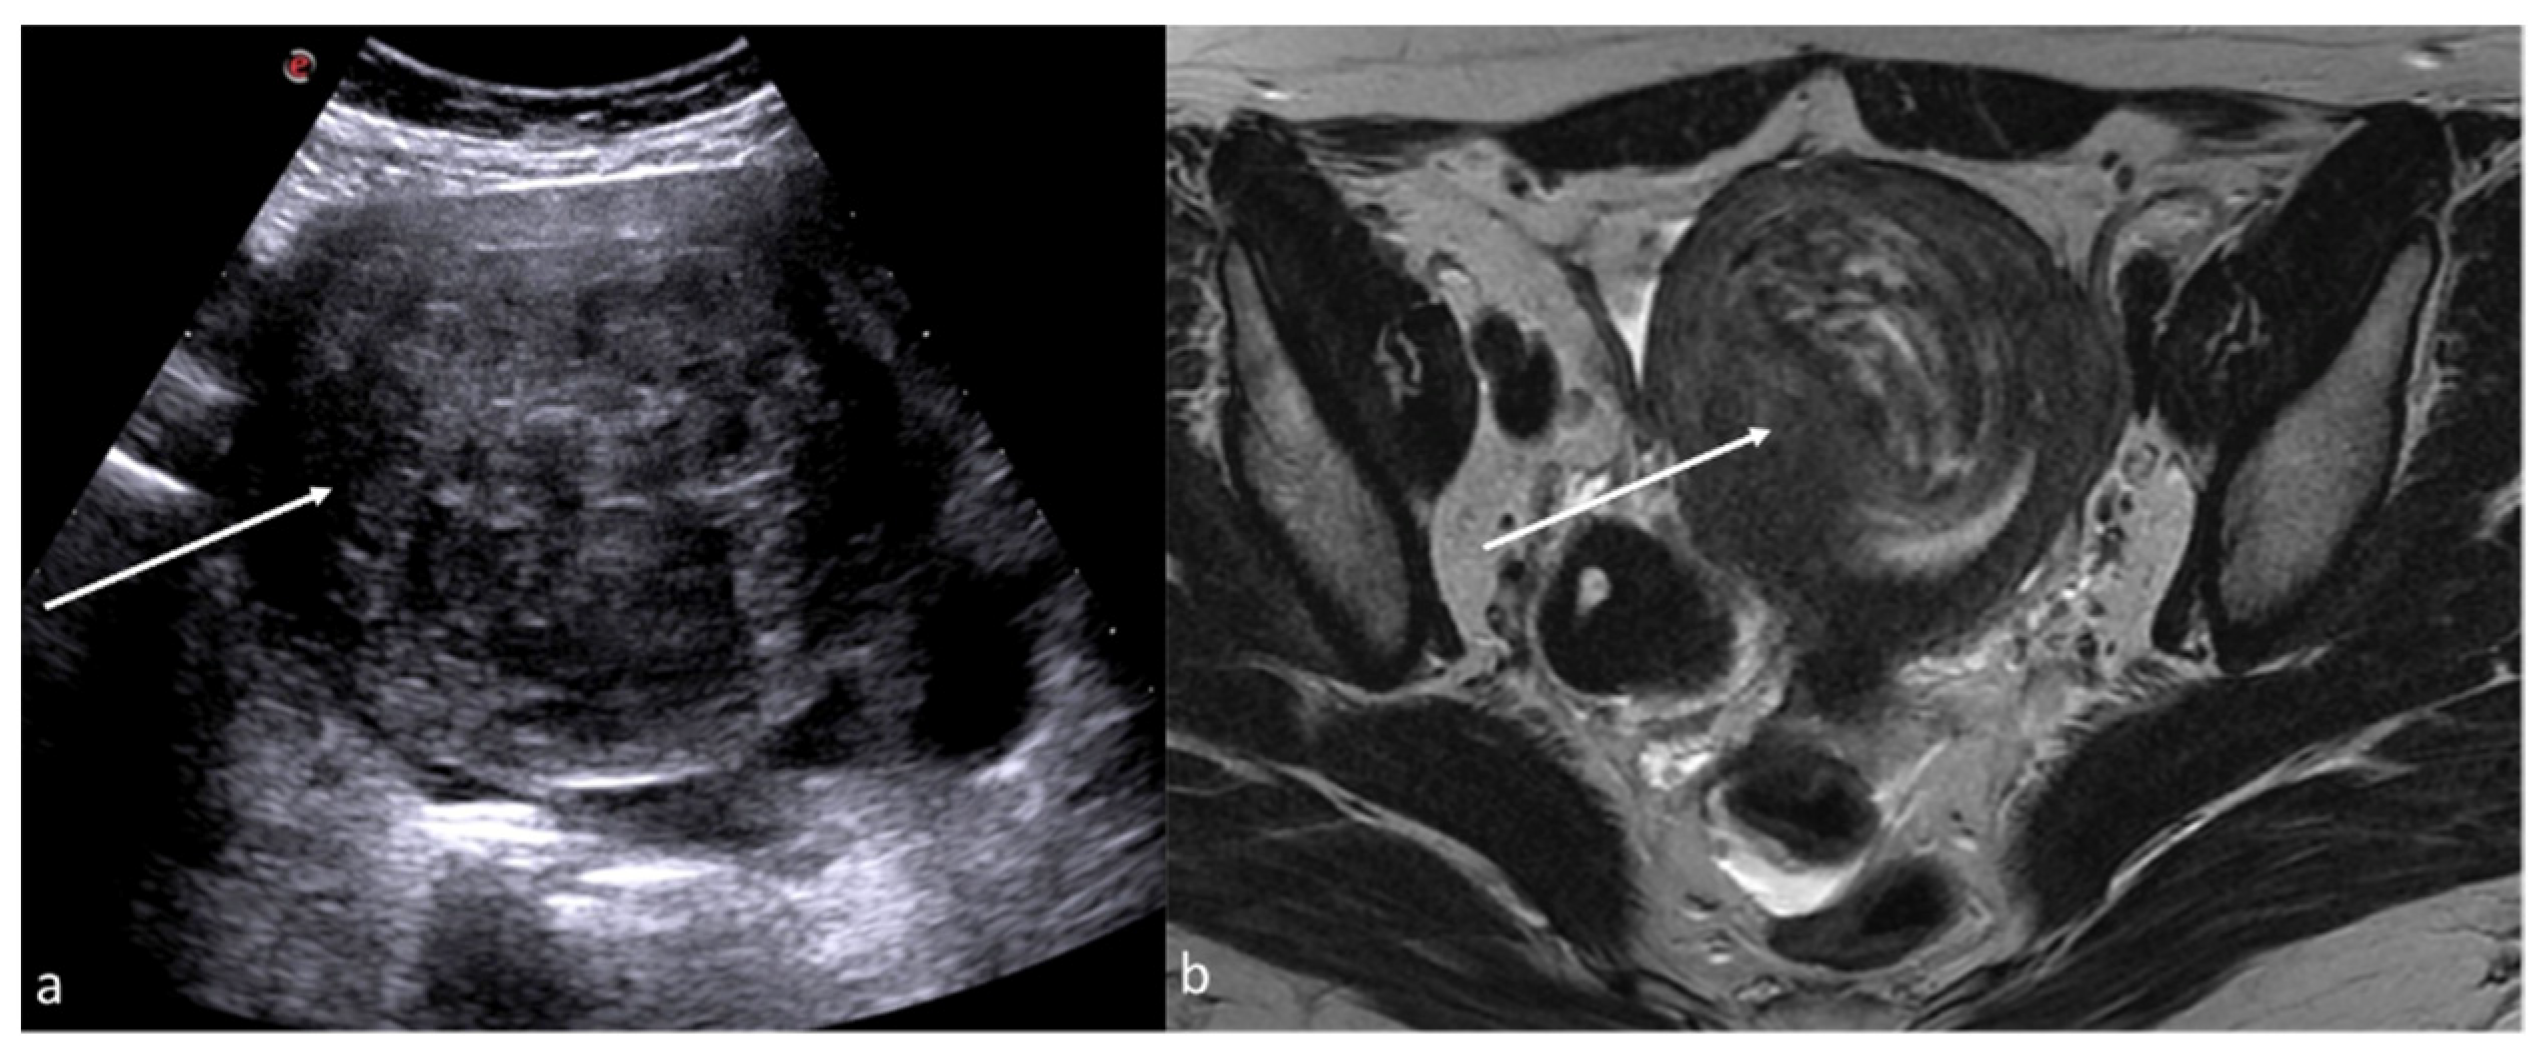

Figure 7. Pyometra. TSA-US scan of the uterus (a) shows a distended uterine cavity containing complex fluid with echogenic foci (short arrows). Axial T2w MRI imaging (b) confirms the diagnosis showing pus collection into uterine cavity.